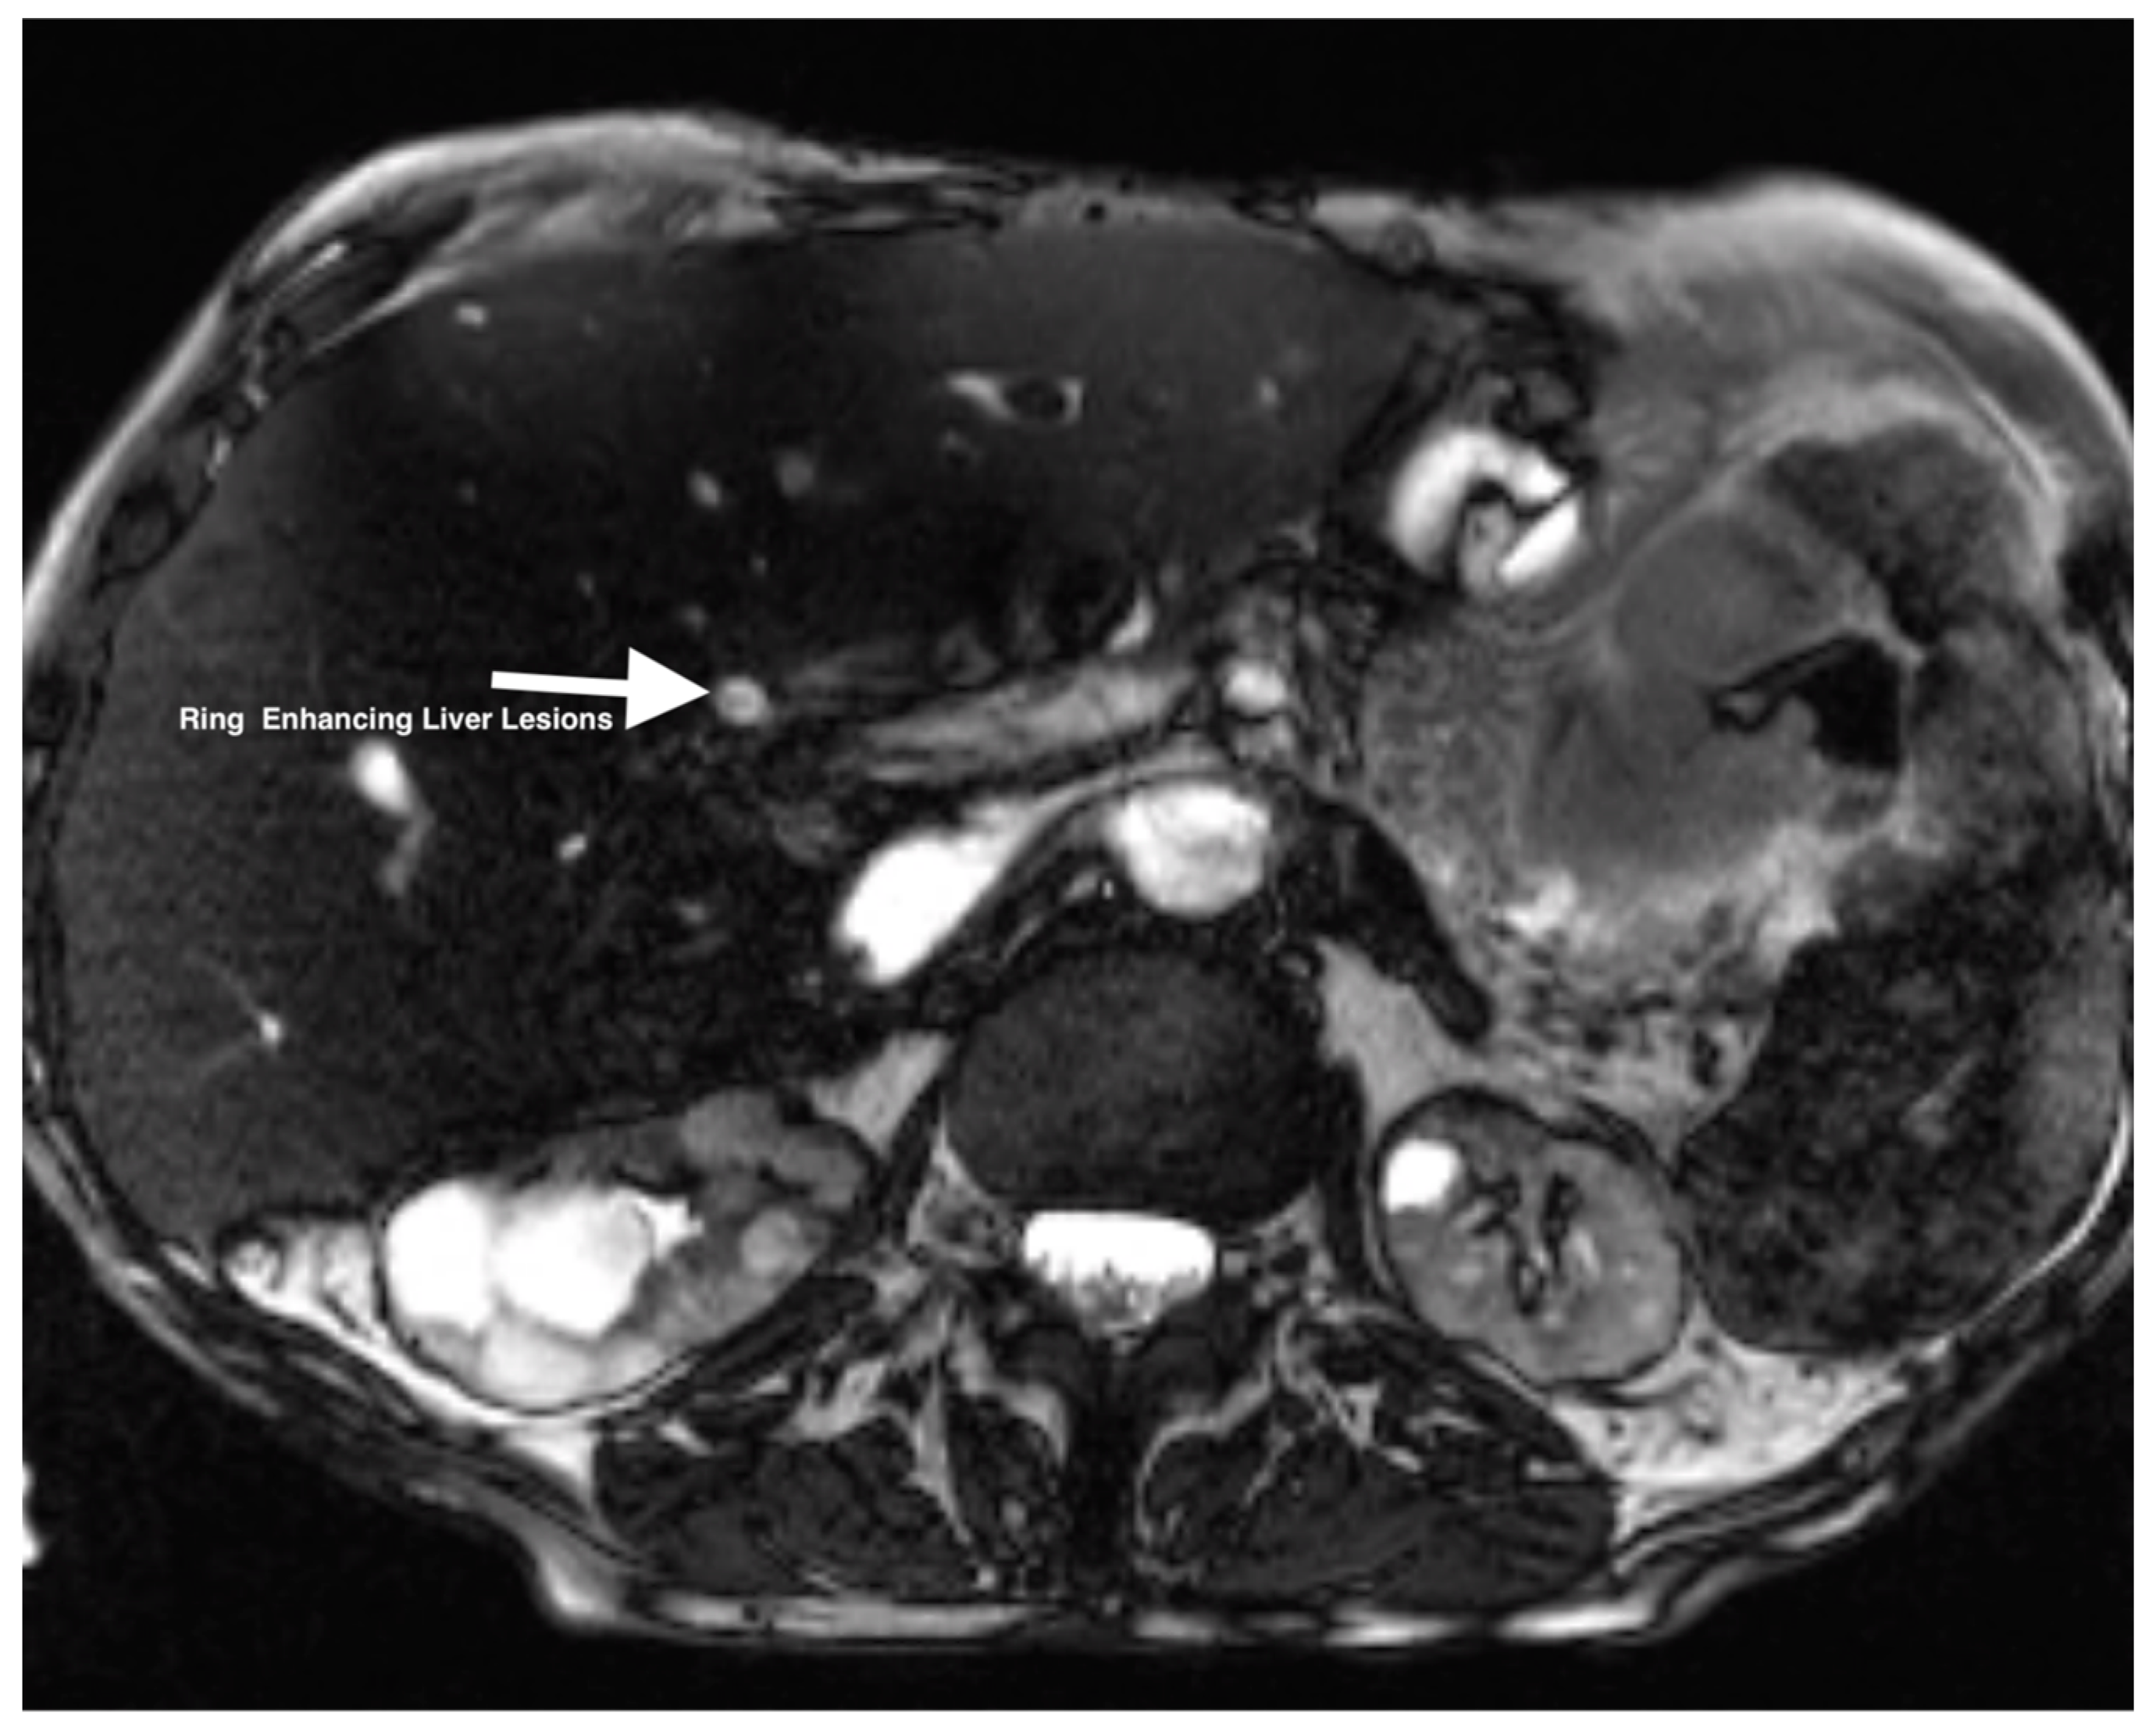

| 2 | CTA abdomen/pelvis | Focus of hyperintensity on the venous phase in the loop of jejunum suggestive of active bleeding without evidence of arterial extravasation. Multiple hypodense lesions throughout the transplanted liver. |

| 2 | US-guided liver biopsy | Consistent with adenocarcinoma with abundant necrosis and multiple clusters of bacteria within the areas of necrosis. |

| 10 | PET-CT (Figure 2 and Figure 3) | Focal intense FDG uptake in the left upper quadrant in the small bowel loop and multifocal FDG avid hepatic metastasis. |